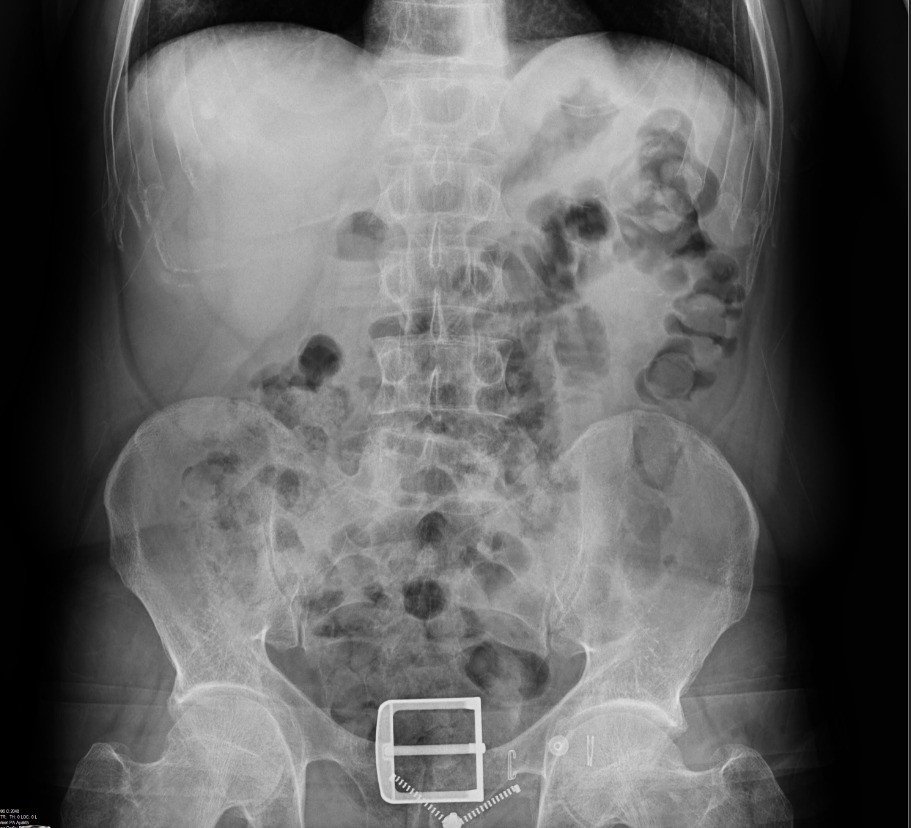

Diyarbakır’da 4 kişinin sindirim sisteminden 840 gram eroin ele geçirildi: 4 kişi tutuklandı

Diyarbakır'da şüpheli 4 kişinin sindirim sisteminden 121 parça halinde 840 gram eroin ele geçirildi.

Diyarbakır'da şüpheli 4 kişinin sindirim sisteminden 121 parça halinde 840 gram eroin ele geçirildi. Gözaltına alınan şüpheliler tutuklandı.

Araçta bulunan 4 şahsın ilk etapta yapılan kaba üst aramalarında herhangi bir suç unsuruna rastlanılmadı. Şahısların tedirgin haller sergilemesi ve rahatsızlık belirtisi vermeleri üzerine, adli makamlardan alınan karara istinaden yapılan tıbbi kontrollerde şüphelilerin vücut boşluğu/sindirim sisteminde 121 parça halinde 840 gram eroin ele geçirildi.